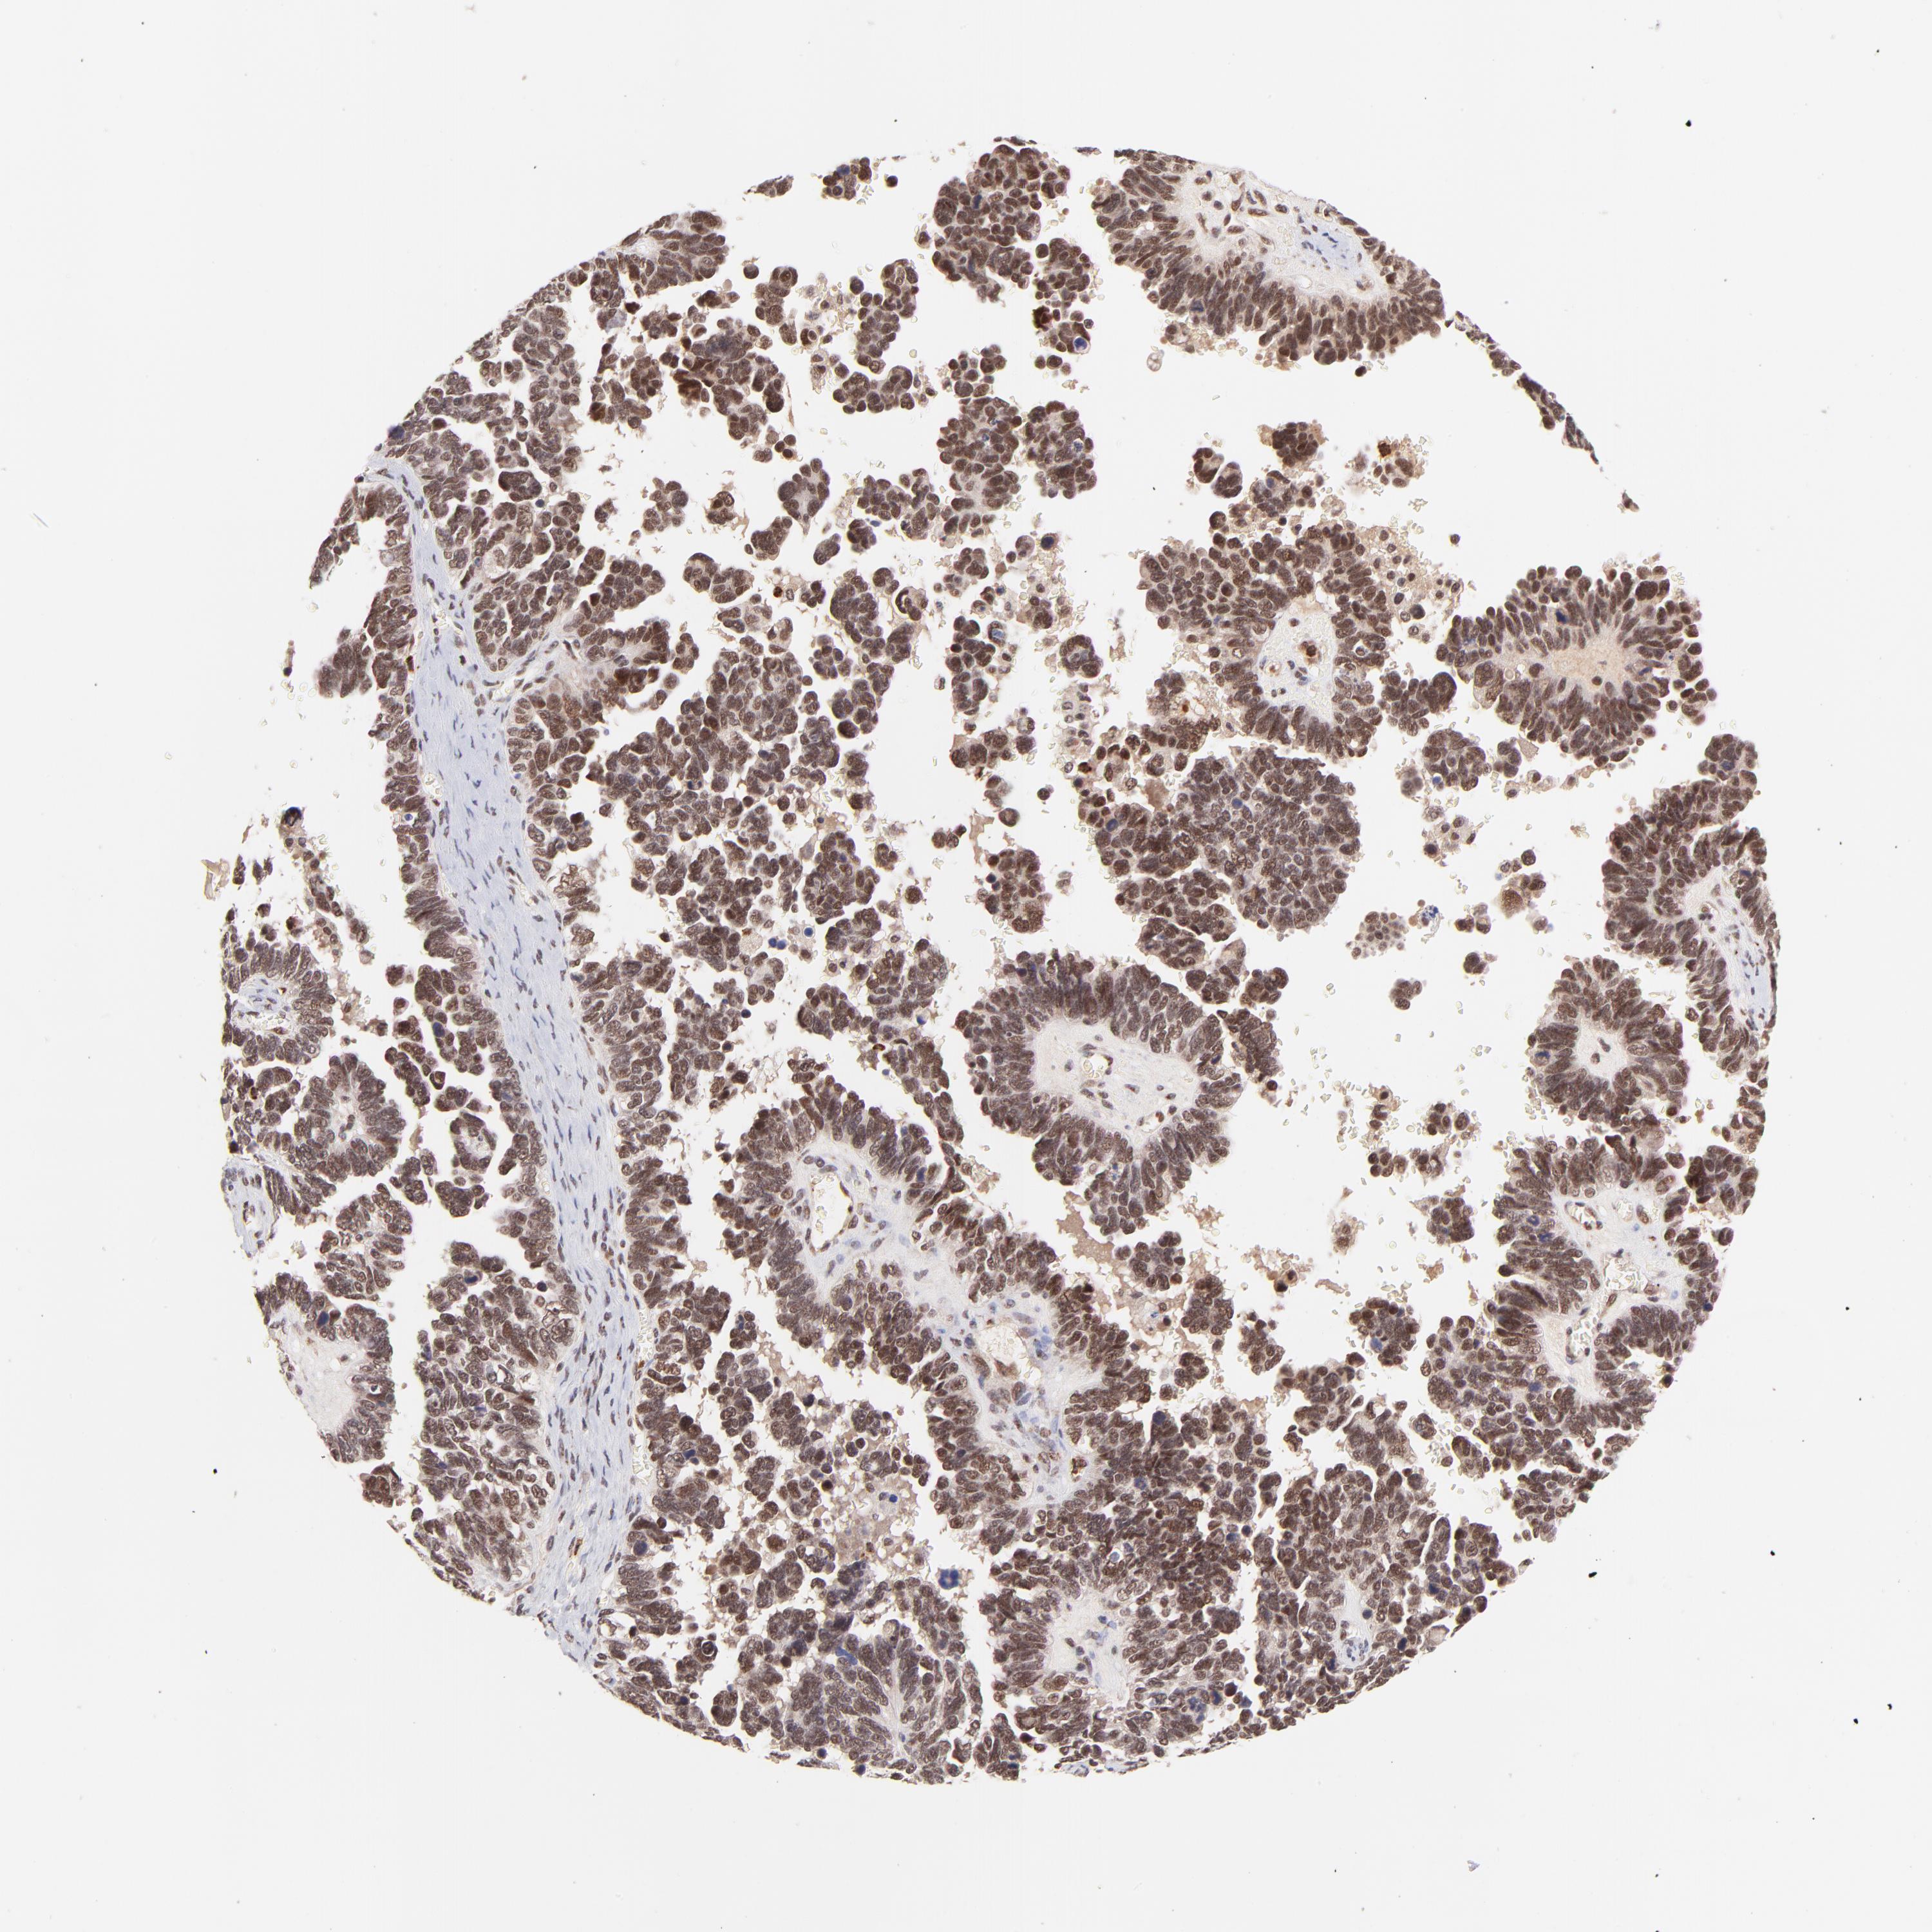

OVARIAN CANCER - Protein expressioni

A mouse-over function shows sample information and annotation data. Click on an image to view it in a full screen mode. Samples can be filtered based on level of antibody staining by selecting one or several of the following categories: high, medium, low and not detected. The assay and annotation is described here.

Note that samples used for immunohistochemistry by the Human Protein Atlas do not correspond to samples in the TCGA dataset.

Antibody stainingi

Antibody staining in the annotated cell types in the current human tissue is reported as not detected, low, medium, or high, based on conventional immunohistochemistry profiling in selected tissues. This score is based on the combination of the staining intensity and fraction of stained cells.

Each image is clickable and will lead to virtual microscopy that enables deeper exploration of all samples and also displays staining intensity scores, fraction scores and subcellular localization as well as patient and tissue information for each sample.

Antibody HPA003184

Antibody HPA003185

Cystadenocarcinoma, mucinous, NOS

Carcinoma, endometroid

Cystadenocarcinoma, serous, NOS